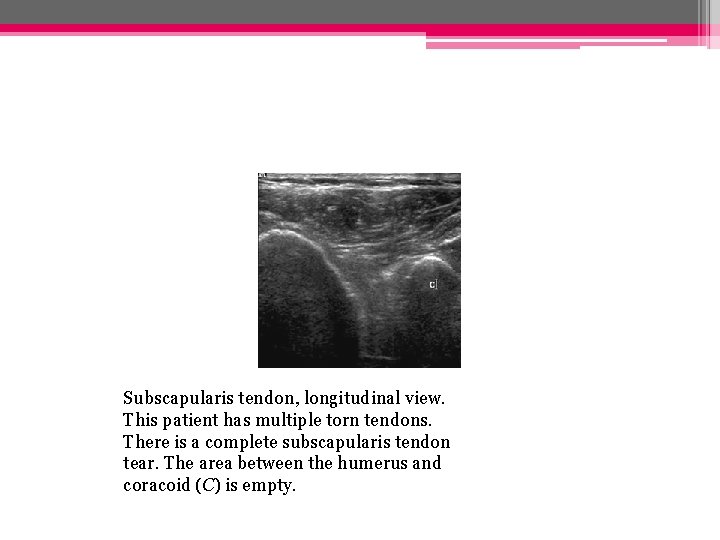

Subscapularis tendon, longitudinal view. This patient has multiple torn tendons. There is a complete subscapularis tendon tear. The area between the humerus and coracoid (C) is empty.